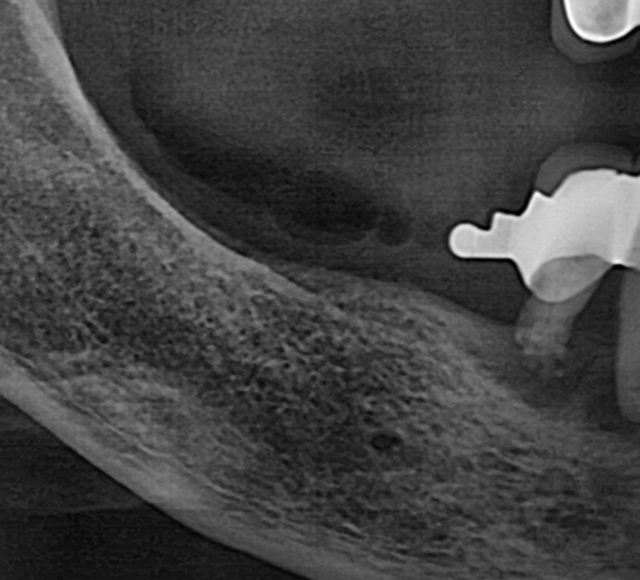

상악동 거상술 케이스

- 얇은 위턱 어금니 부위에 상악동을 거상하여 골량 보강

- 임상 경험을 바탕으로 합병증을 낮추고 예측 가능한 결과 도출